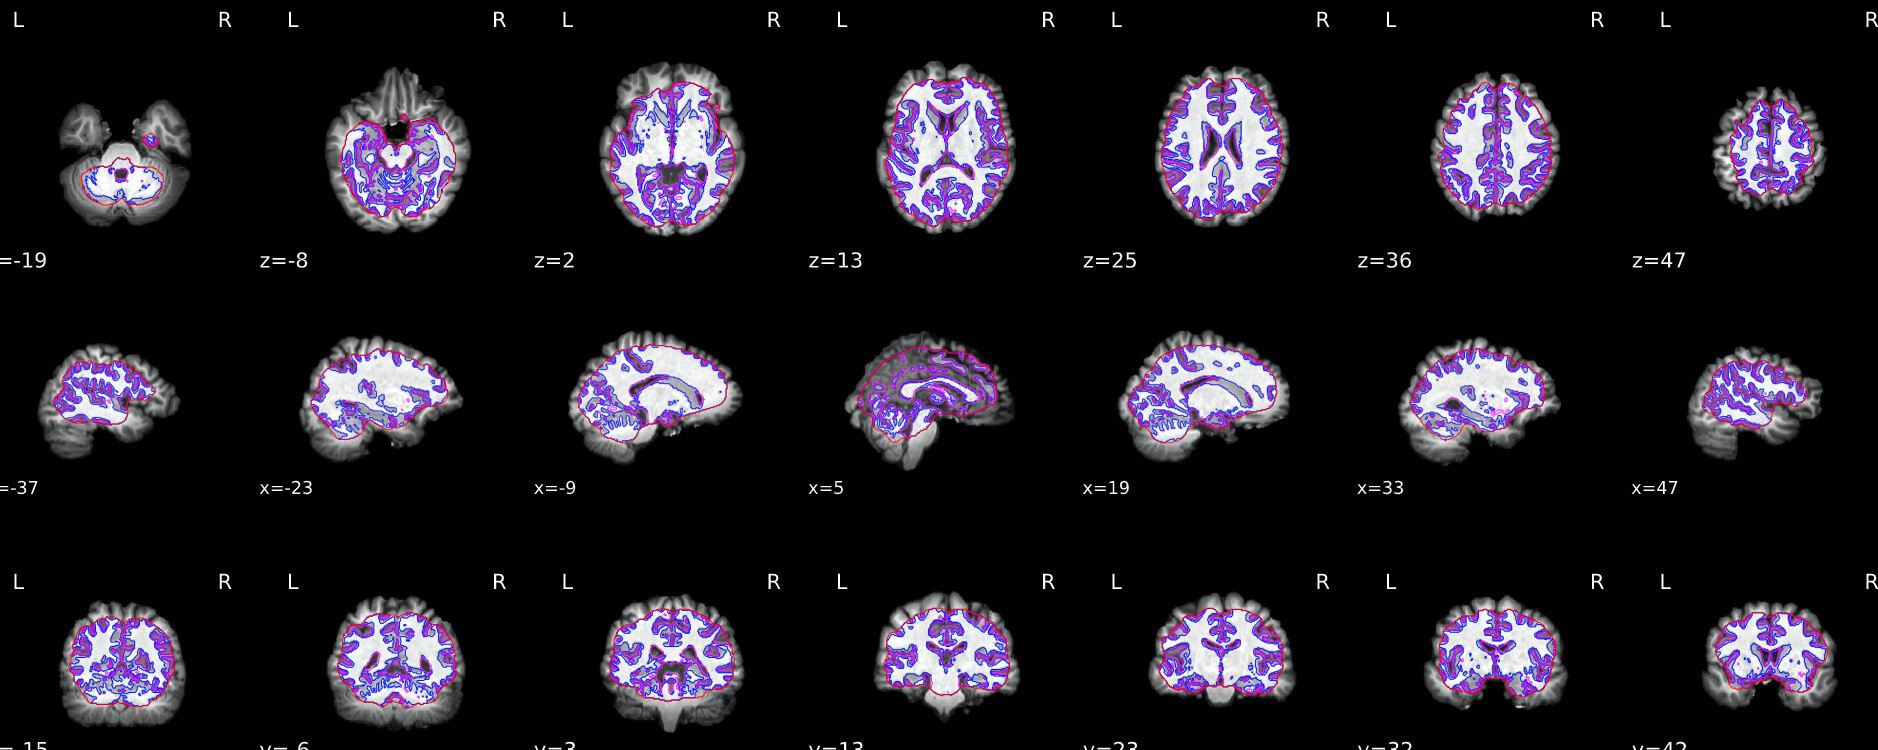

I ran fmriprep on this dataset and the segmentation is not quite right. Is there an issue in the dataset that fmriprep can’t deal with?